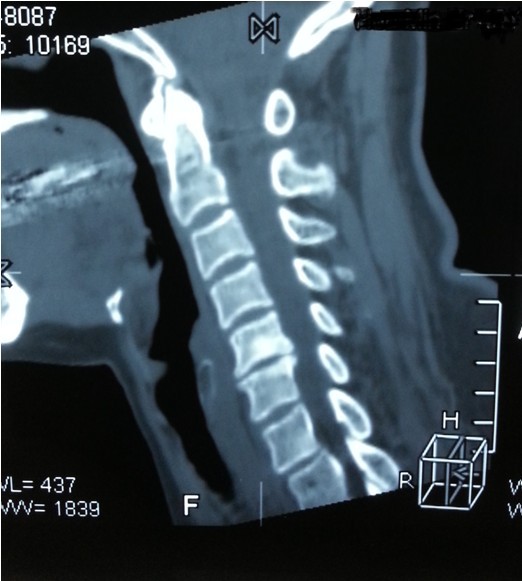

我院副院長兼脊柱科主任劉志安詢問病史后,詳細(xì)查體并攝片,發(fā)現(xiàn)患者是頸椎間盤突出,骨質(zhì)增生,壓迫頸椎神經(jīng),引起頸肩部酸脹難忍,雙手麻木乏力,若不盡快處理,癥狀將進(jìn)一步加重,建議患者盡早手術(shù)治療,否則將喪失最后的手術(shù)時機,有致癱瘓的可能。

一開始,處于對手術(shù)以及住院費用的恐懼,患者要求保守治療,可是如此嚴(yán)重的椎間盤突出,保守治療根本無法解除對頸椎的神經(jīng)的壓迫。劉副院長詳細(xì)向患者講述其病情起因,發(fā)展,變化,轉(zhuǎn)歸,并表示,患者頸椎手術(shù)總費用預(yù)計在5萬以內(nèi),報銷后自費約4萬左右,考慮患者家庭困難,可聯(lián)系紅十字基金會予以適當(dāng)?shù)难a貼,考慮再三,最終患者選擇到我院手術(shù)治療。手術(shù)結(jié)束后,患者慢慢開始恢復(fù),頸肩部酸脹不適癥狀消失,雙手麻木乏力癥狀較術(shù)前大為緩解,兩周后出院,患者及家屬對手術(shù)治療效果,醫(yī)生護(hù)士服務(wù)態(tài)度,以及花了3萬元就解決困擾多年的疾病均表示非常滿意。